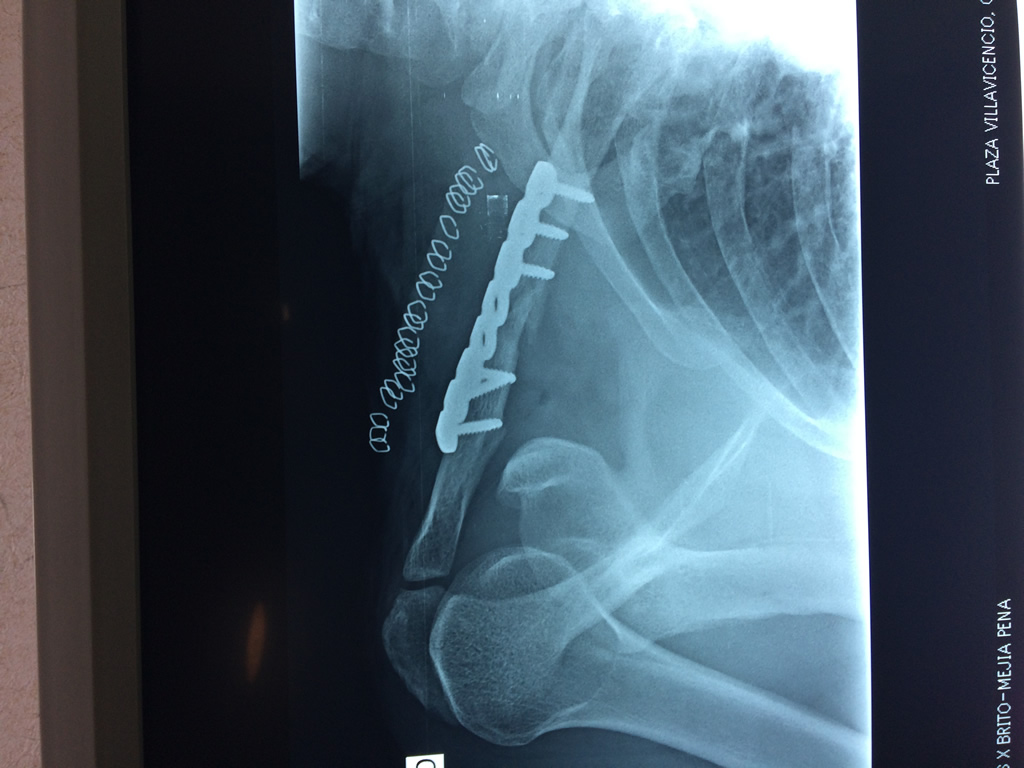

Cirugías de Hombros - Clavícula

La clavícula es un hueso largo, con forma de "S" itálica, situado en la parte anterosuperior del tórax. Junto con la escápula forman la cintura escapular. Se puede palpar por toda su longitud y se extiende del esternón al acromion de la escápula, siguiendo una dirección oblicua lateral y posterior.